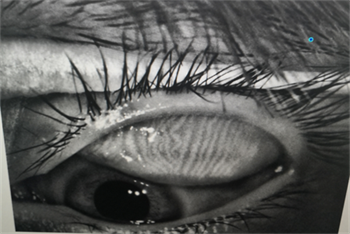

06、螨蟲檢查

每一個(gè)眼瞼拔3根睫毛,檢查有沒有蠕形螨,以及數(shù)量多少。

如果任意一個(gè)眼瞼螨蟲數(shù)量不少于3只,就需要除螨治療了。眼瞼螨蟲過多會(huì)造成機(jī)械性損傷,附帶細(xì)菌還會(huì)引起瞼緣感染,后續(xù)會(huì)有干癢、紅腫、分泌物增多、睫毛脫落等一系列問題。